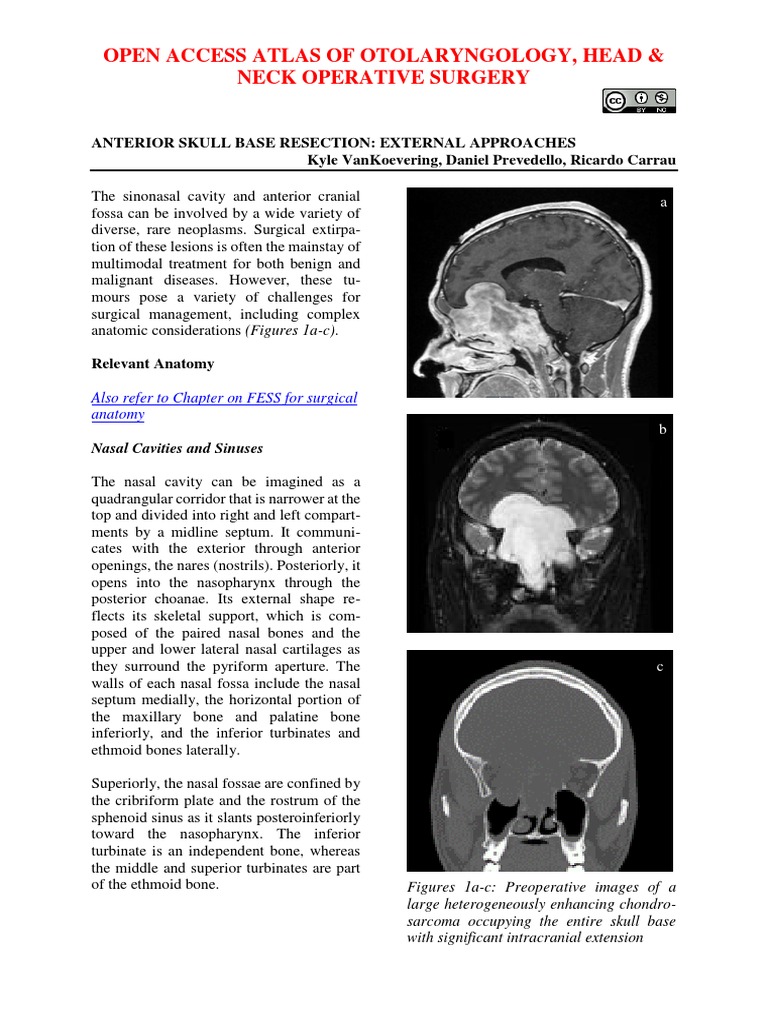

1.32: Anterior Skull Base Resection- External Approaches - Medicine ...

Anterior Skull Base Resection External Approaches | PDF | Human Nose ...